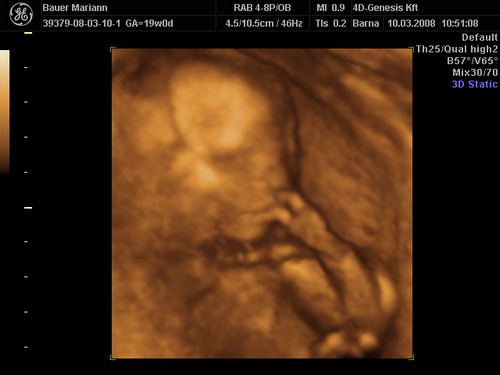

[quote="mpatr"][ írta:mpatrb]Nici, a felvétel élessége és sikerültsége sok mindentől függ.

A profi gépen túl a profi és türelmes szonográfus, a lepény és baba helyzete (mellső fali lepénynél kicsit nehezebb az ügy, meg a babák is imádnak belebújkálni a lepénybe), a magzatvíz mennyisége, a mama hasfalának zsírrétege (mennyire dagi anyuci) szóval ezek (biztos van még) min-mind befolyásolják a felvétel minőségét.

Nekem sikerült ugyanarról a gyerkőcről aki a pocimban van nagyon tuti és nagyon sz..r képet is készíteni ugyanazzal a géppel.

Érdemes többször próbálkozni.